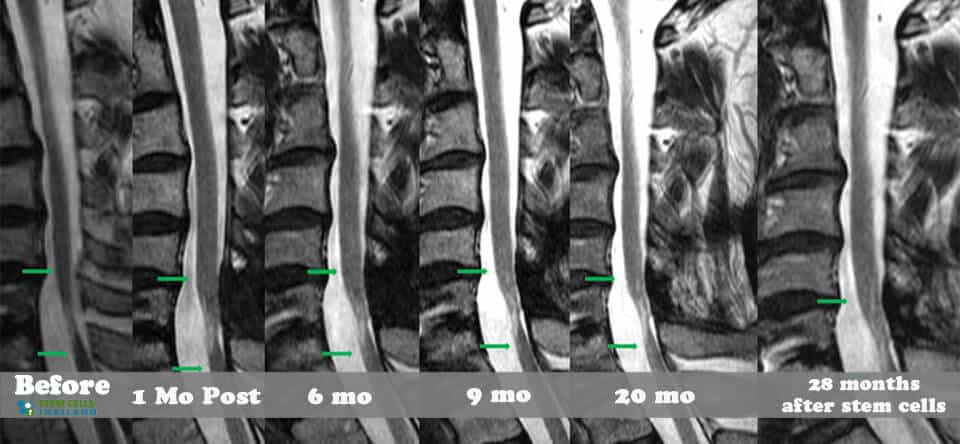

脊髓損傷的細胞療法側重于大腦和身體之間軸突的再生,這些軸突在事故發生后受到嚴重限制或不存在。我們針對脊髓損傷的干細胞移植可以幫助患者消除疼痛,恢復膀胱和腸道功能,恢復失去的感覺,并再生內臟運動神經元,同時最大限度地減少其他問題,例如損傷引起的痙攣或抑郁。傳統治療不解決再生問題,而是側重于疼痛管理、康復和減少繼發性損傷。

基于細胞的治療采取更積極主動的方法,通過刺激/增強受損細胞和組織的修復來促進人類的自然修復周期。修復受傷的脊髓和竹脊柱需要超越任何傳統技術來幫助您恢復部分/全部失去的功能。臨床試驗表明,細胞更新和死亡是非常正常的,當身體細胞受傷或老化時,細胞會自然發生。這些死亡細胞通常被健康和受損的細胞包圍。我們針對坐骨神經痛和椎管狹窄的治療方案通過利用神經生長因子和旁分泌信號傳導的靶向細胞因子療法,有助于促進這些死亡或受傷細胞的愈合欺騙身體重新開始愈合過程。

對于具有廣泛神經細胞萎縮的嚴重病例,治療需要通過CT引導的脊柱內機器將擴增的MSC+間充質干細胞和神經細胞生長因子注射到受損的脊柱區域附近。針對脊髓損傷的MSC+方案是獨一無二的,因為它是世界上唯一提供補充注射神經細胞特異性生長因子的治療方法,根據損傷的嚴重程度,使用腰椎穿刺、鞘內注射或靜脈滴注進一步促進康復。

增強型MSC+干細胞注射是現代再生醫學的白金標準,尤其是在處理脊髓橫斷時。細胞引導的精確性使我們的團隊能夠直接瞄準鄰近的病變或損傷區域。MSC+增強型脊柱治療不需要危險的開放性脊柱手術。MSC+干細胞注射和神經祖細胞輸注還可以幫助患者避免與傳統治療脊髓損傷相關的額外手術的風險和痛苦。[1]

組織、軟骨或韌帶的新損傷對干細胞治療的反應要好得多。治療后的康復需要大量的奉獻和康復訓練。初次治療后約2-3個月,身體改善明顯,且效果是永久性的。[2]